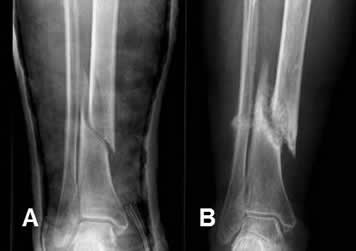

Fig 122. Consolidación retardada.

A: Rx AP. Fractura espiroidea en la tibia, que se manejó con reducción cerrada y estabilización con yeso.

B: Rx AP. Rx de control a los 4 meses, sin formación de callo óseo y los extremos no están en contacto.